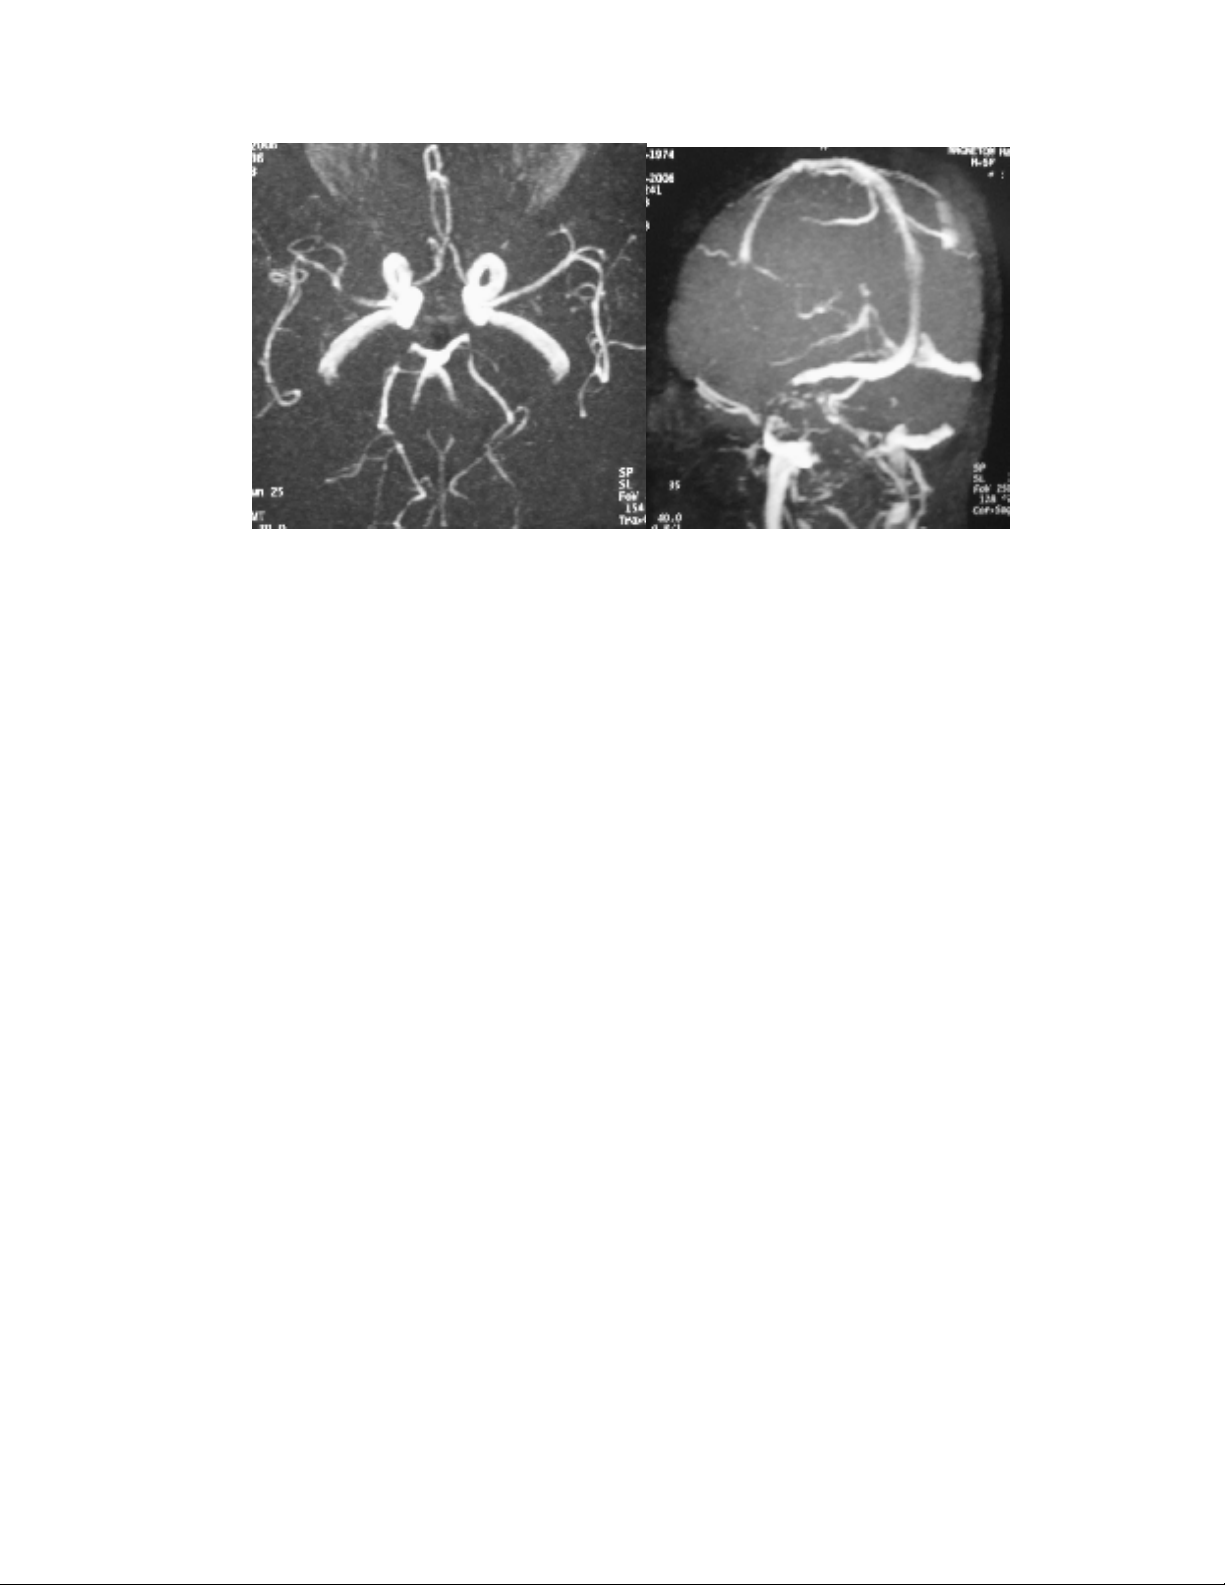

- MRA: Heïp ñoäng maïch naõo giöõa P, caùc ñoäng maïch naõo ñöôøng kính khoâng ñeàu, to

nhoû töøng ñoaïn.

Hình 1: Hình aûnh CT, MRI, MRA, vaø MRV cho thaáy toån thöông vuøng chaåm phaûi > traùi, ñoäng

maïch to nhoû nhieàu ñoaïn, vaø tónh maïch khoâng coù baát thöôøng.